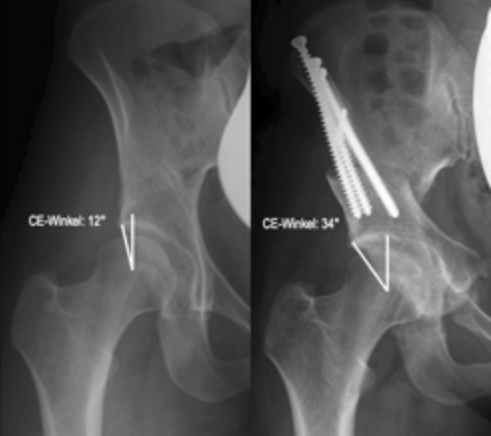

Дисплазия тазобедренного сустава относится к неправильному росту во внутренней полости тазобедренного сустава. Это также может привести к плохой осанке, которая известна как вывих бедра или вывих бедренного сустава. Головка бедра частично или полностью удалена относительно внутренней полости тазобедренного сустава, что означает, что головка не присутствует должным образом во внутренней полости, как показано на следующих изображениях.

Это может привести к повышению давления на область полости, что может вызвать преждевременный износ суставного хряща, что иногда требует замены сустава в раннем возрасте.Лечение: на ранней стадии с незначительным повреждением суставного хряща, есть возможность исправить это отклонение с помощью трехмерных пятен таза, как показано на следующих изображениях.